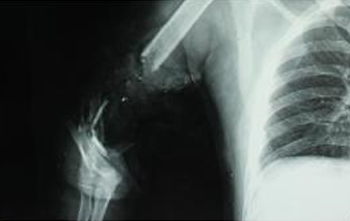

◎ 四肢骨折 |

◎ 四肢骨折的微创治疗 |

擅长:严重四肢骨折,小儿骨折,老年人骨折的治疗,肢体严重创伤显微修复及功能重建,特殊类型断指(肢)再植,拇手指再造,小儿先天性畸形矫形、烧伤瘢痕整形,四肢骨缺损、难治性创面修复,褥疮、糖尿病足的治疗,手部各种肿瘤、神经损伤的修复

擅长:四肢创伤的显微外科修复;各种类型的断指(肢)再植,小儿断指(肢)再植;肢体严重创伤的修复与功能重建;各类游离皮瓣、岛状皮瓣移植修复及瘢痕修整;膝关节关节镜外科的疾病诊断及治疗;四肢骨折、脊椎骨折及人工髋关节置换的疾病诊断及治疗